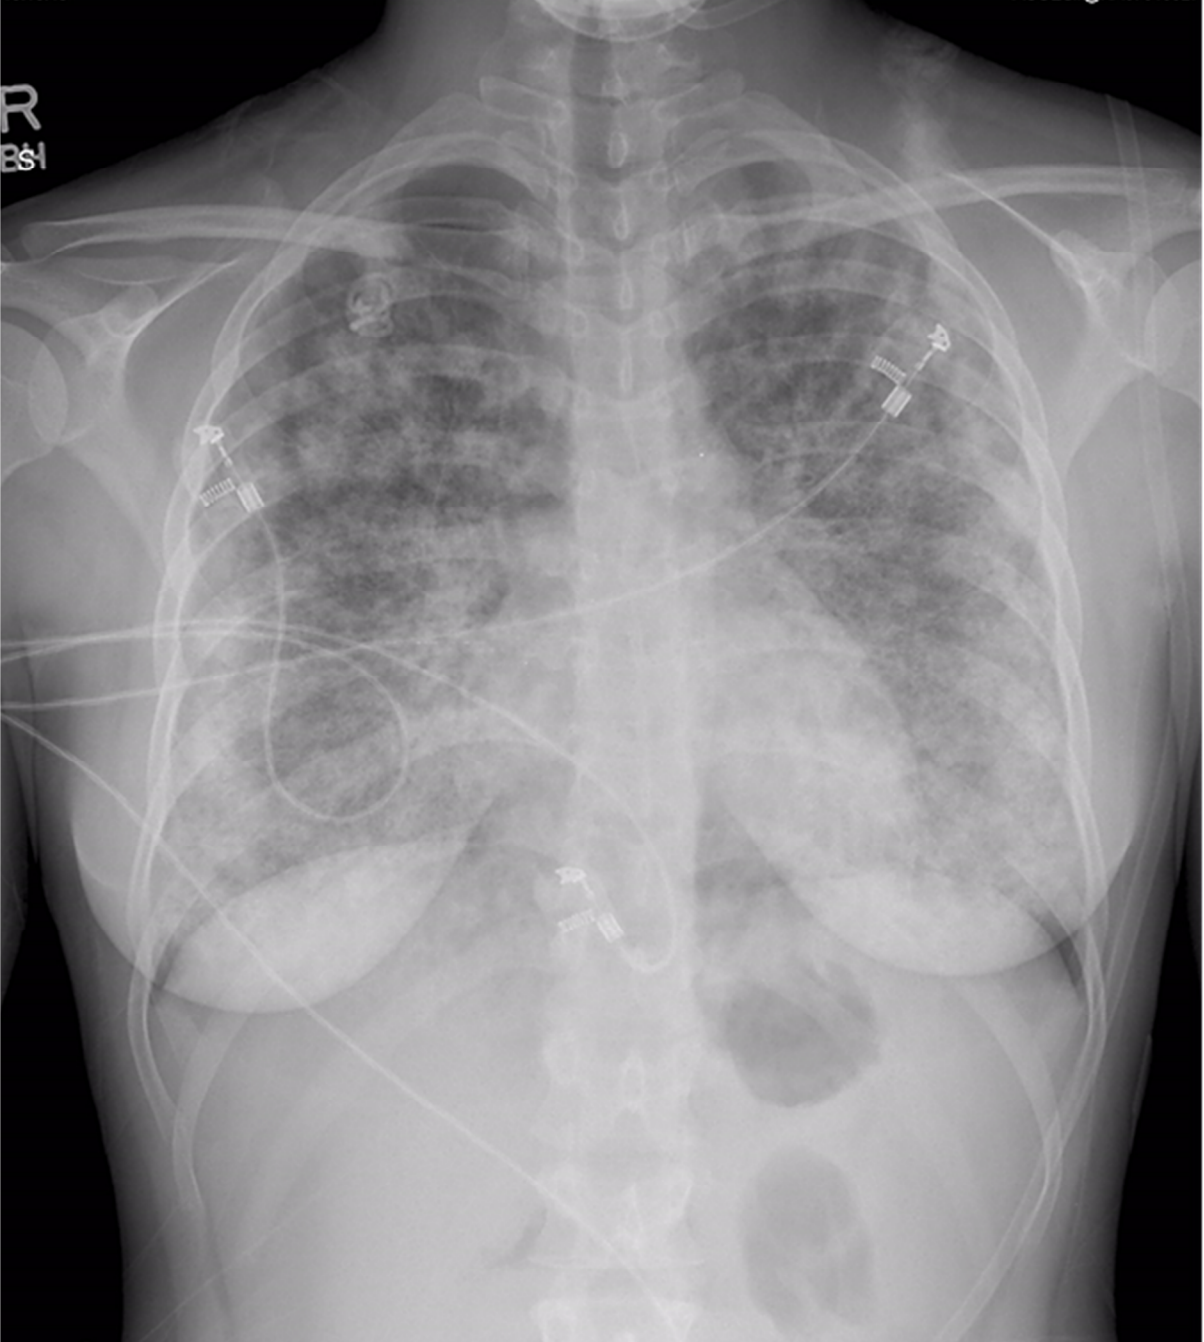

CXR - 30M IVDU - Describe xray and differential

1. Cavitating lesion RMZ 2. RML-LL consolidation 3. Air bronchogram 4. Small right pleural effusion 5. Fluid in horizontal fissure DDx. Infective: - Staph aureus - TB/mycoplasma - Anaerobes (peptostreptococcus etc.) - Gram negs: klebsiella/legionella/pseudomonas etc. - Strep pneumo - Fungal, cryptococcosis, parasites, PJP Non-infectious: - Malignancy (primary, metastatic, lymphoma) - Vascular incl. pulmonary infarction, VTE - Granulomas (RA, sarcoidosis, Wegener's) - Pneumoconiosis, bronchiectasis - Congenital cyst